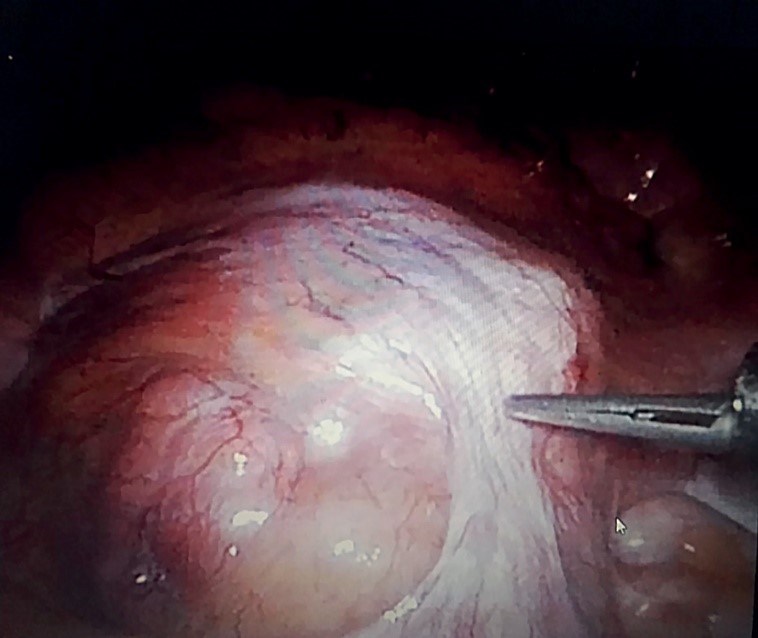

3. Рисунок 3. Диссекция новообразования.

Тема

Тип Исследовательские инструменты

Посмотреть (117KB)